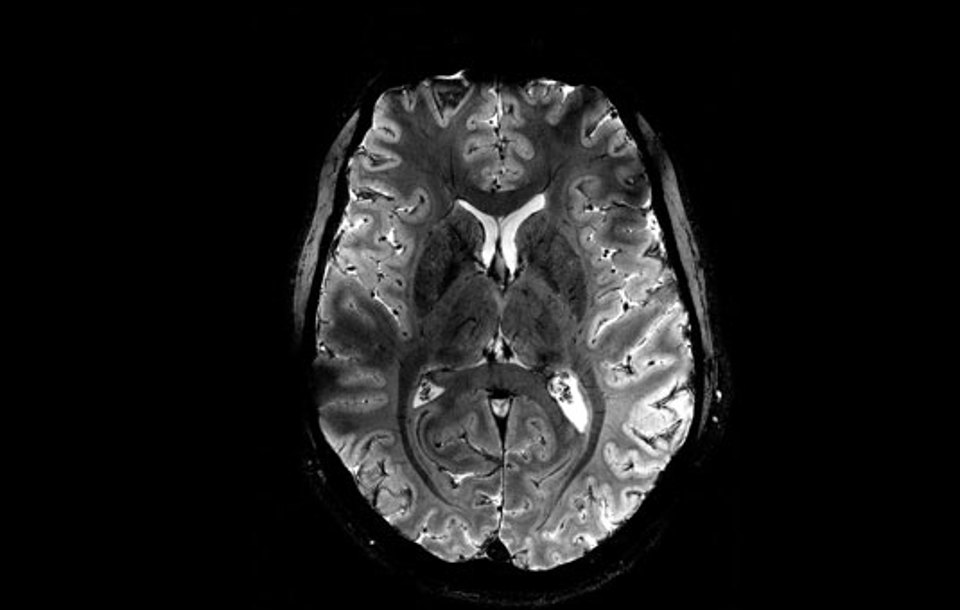

11.7 Тесла хүчин чадалтай шинэ Iseult MRI төхөөрөмжөөр авсан тархины зургийн нарийвчлалын түвшнийг харуулж байна. (Зураг: CEA)

Францын Алтернатив эрчим хүч ба атомын энергийн комисс (CEA) 11.7 тесла соронзон орны хүчин чадалтай дэлхийн хамгийн хүчирхэг сканер болох Iseult соронзон резонансын дүрслэл (MRI) аппаратыг ашиглан авсан тархины цоо шинэ зургуудыг дэлгэлээ. Хорин жилийн турш явагдаж буй уг төсөл нь тархи судлалд томоохон ахиц дэвшил гаргах зорилготой юм.

Уг төхөөрөмж нь эмнэлгүүдэд одоогоор ашиглагдаж буй 1.5 эсвэл 3 тесла, соронзон орны бага хүчин чадалтай MRI сканертай харьцуулахад ердөө дөрвөн минутын дотор маш нарийвчилсан анатомийн зургийг гаргах чадалтай юм.